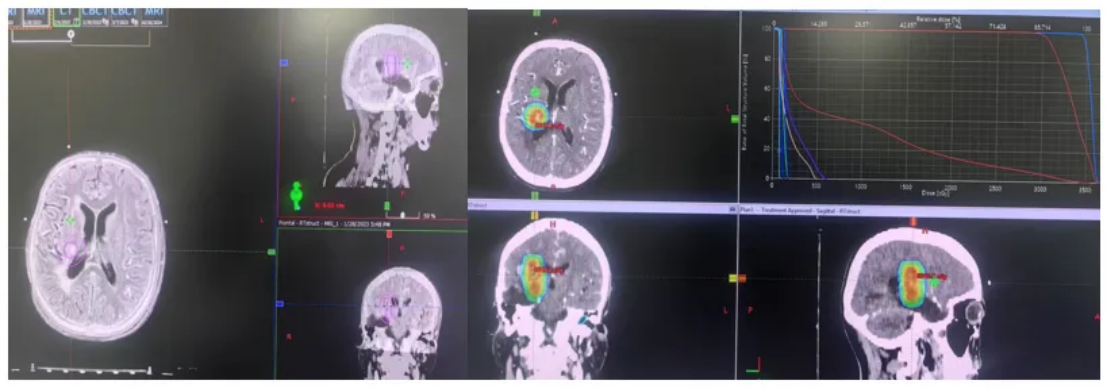

2023-6-15随访复查颅脑MRI平扫+增强:右侧颞叶胶质瘤术后;右侧基底节区后部点状异常信号,较前(2023-3-28)缩小;右侧大脑脚华勒氏变性;右侧侧脑室周围及胼胝体压部缺血灶;右侧基底节区陈旧性腔梗灶;右侧基底节区亚急性腔梗灶?(图6)

图6 颅脑MRI图像

2023-9-22脑部MRI随访复查:右侧颞叶胶质瘤术后;右侧基底节区后部点状异常信号,较前(2023-06-15)相仿,建议定期复查;右侧大脑脚华勒氏变性;桥脑小片状异常信号,较前新发,软化灶伴出血?转移待排;右侧胼胝体压部及桥脑急性腔梗,较前新发,随诊复查;右侧侧脑室周围缺血灶;右侧基底节区陈旧性腔梗灶;两侧筛窦炎(图7)。

图7 颅脑MRI图像

2023-12-29脑部MRI随访复查:右侧颞叶胶质瘤术后;右侧基底节区后部点状异常信号,较前(2023-09-22)相仿,建议定期复查;右侧大脑脚华勒氏变性;桥脑小片状异常信号,较前增大,软化灶并含铁血黄素沉积?转移待排;右侧侧脑室边缘及左侧基底节异常信号,急性腔梗可能,较前新发,随诊复查;右侧侧脑室周围缺血灶;右侧基底节区陈旧性腔梗灶;两侧筛窦炎(图8)。

图8 颅脑MRI图像